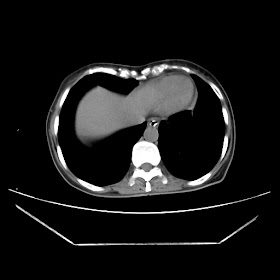

Radiological images:

CT-Scan investigation done on 16Apr16